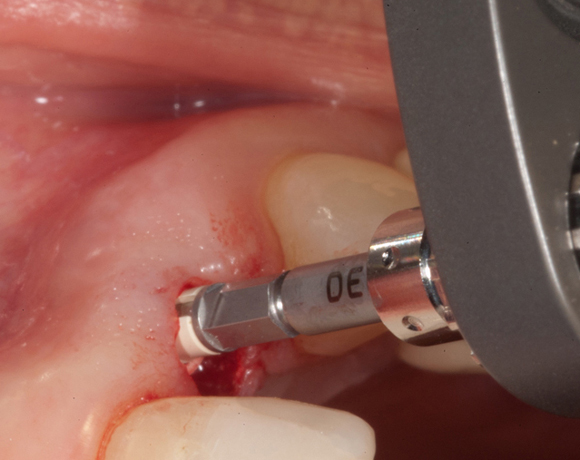

Zeramex T Implantat für Zahn 22

Ein Projekt aus dem Jahr 2013

Im vorliegenden Patientenfall musste der Zahn 22 nach erfolgloser Endodontie entfernt werden. Die Nachbarzähne waren kariesfrei, es wurde eine Marylandbrücke (eine Brücke mit zwei Flügelchen, die palatinal an den Nachbarzähnen verklebt werden) oder ein Implantat besprochen. Die Patientin hat sich für ein Vollkeramikimplantat entschieden. In der Diashow wird der operative Eingriff bis zur fertigen Krone gezeigt. Die Einheilzeit betrug drei Monate.